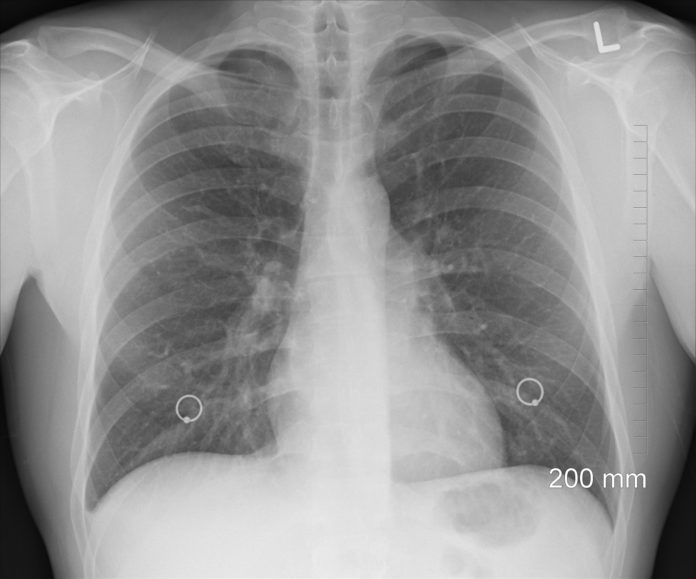

Iako simptomi često nisu jasni važno je da li se uporno javljaju. Simptome koji prate rak pluća često pripisujemo manje ozbiljnim bolestima, ipak ako barem dve nedelje osećate neku od ove četiri tegobe trebalo bi da odete kod lekara na pregled.

Iako je teško pripisati telesne senzacije samom karcinomu, lekari su retrospektivno analizirali izveštaje 61 osobe sa dijagnozom raka pluća u Danskoj, Engleskoj i Švedskoj. Prema istraživačima, izdvojila su se četiri simpotma: umor, gubitak daha, bol u grudima i kašalj.

Lekari upozoravaju da su ovo crvene zastavice koje nam organizam šalje i koje zahtevaju detaljniji pregled.